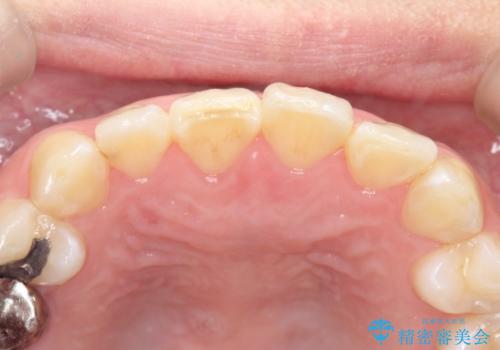

- 前歯の歯並びが気になるとのことで来院されました。

右上の1番目の歯が内側に入り込んでしまっており、その歯がの先端がすり減ってしまっていました。

インビザラインによる矯正治療で前歯の歯並びを改善し、セラミッククラウン装着により歯の形態の回復をする計画としました。